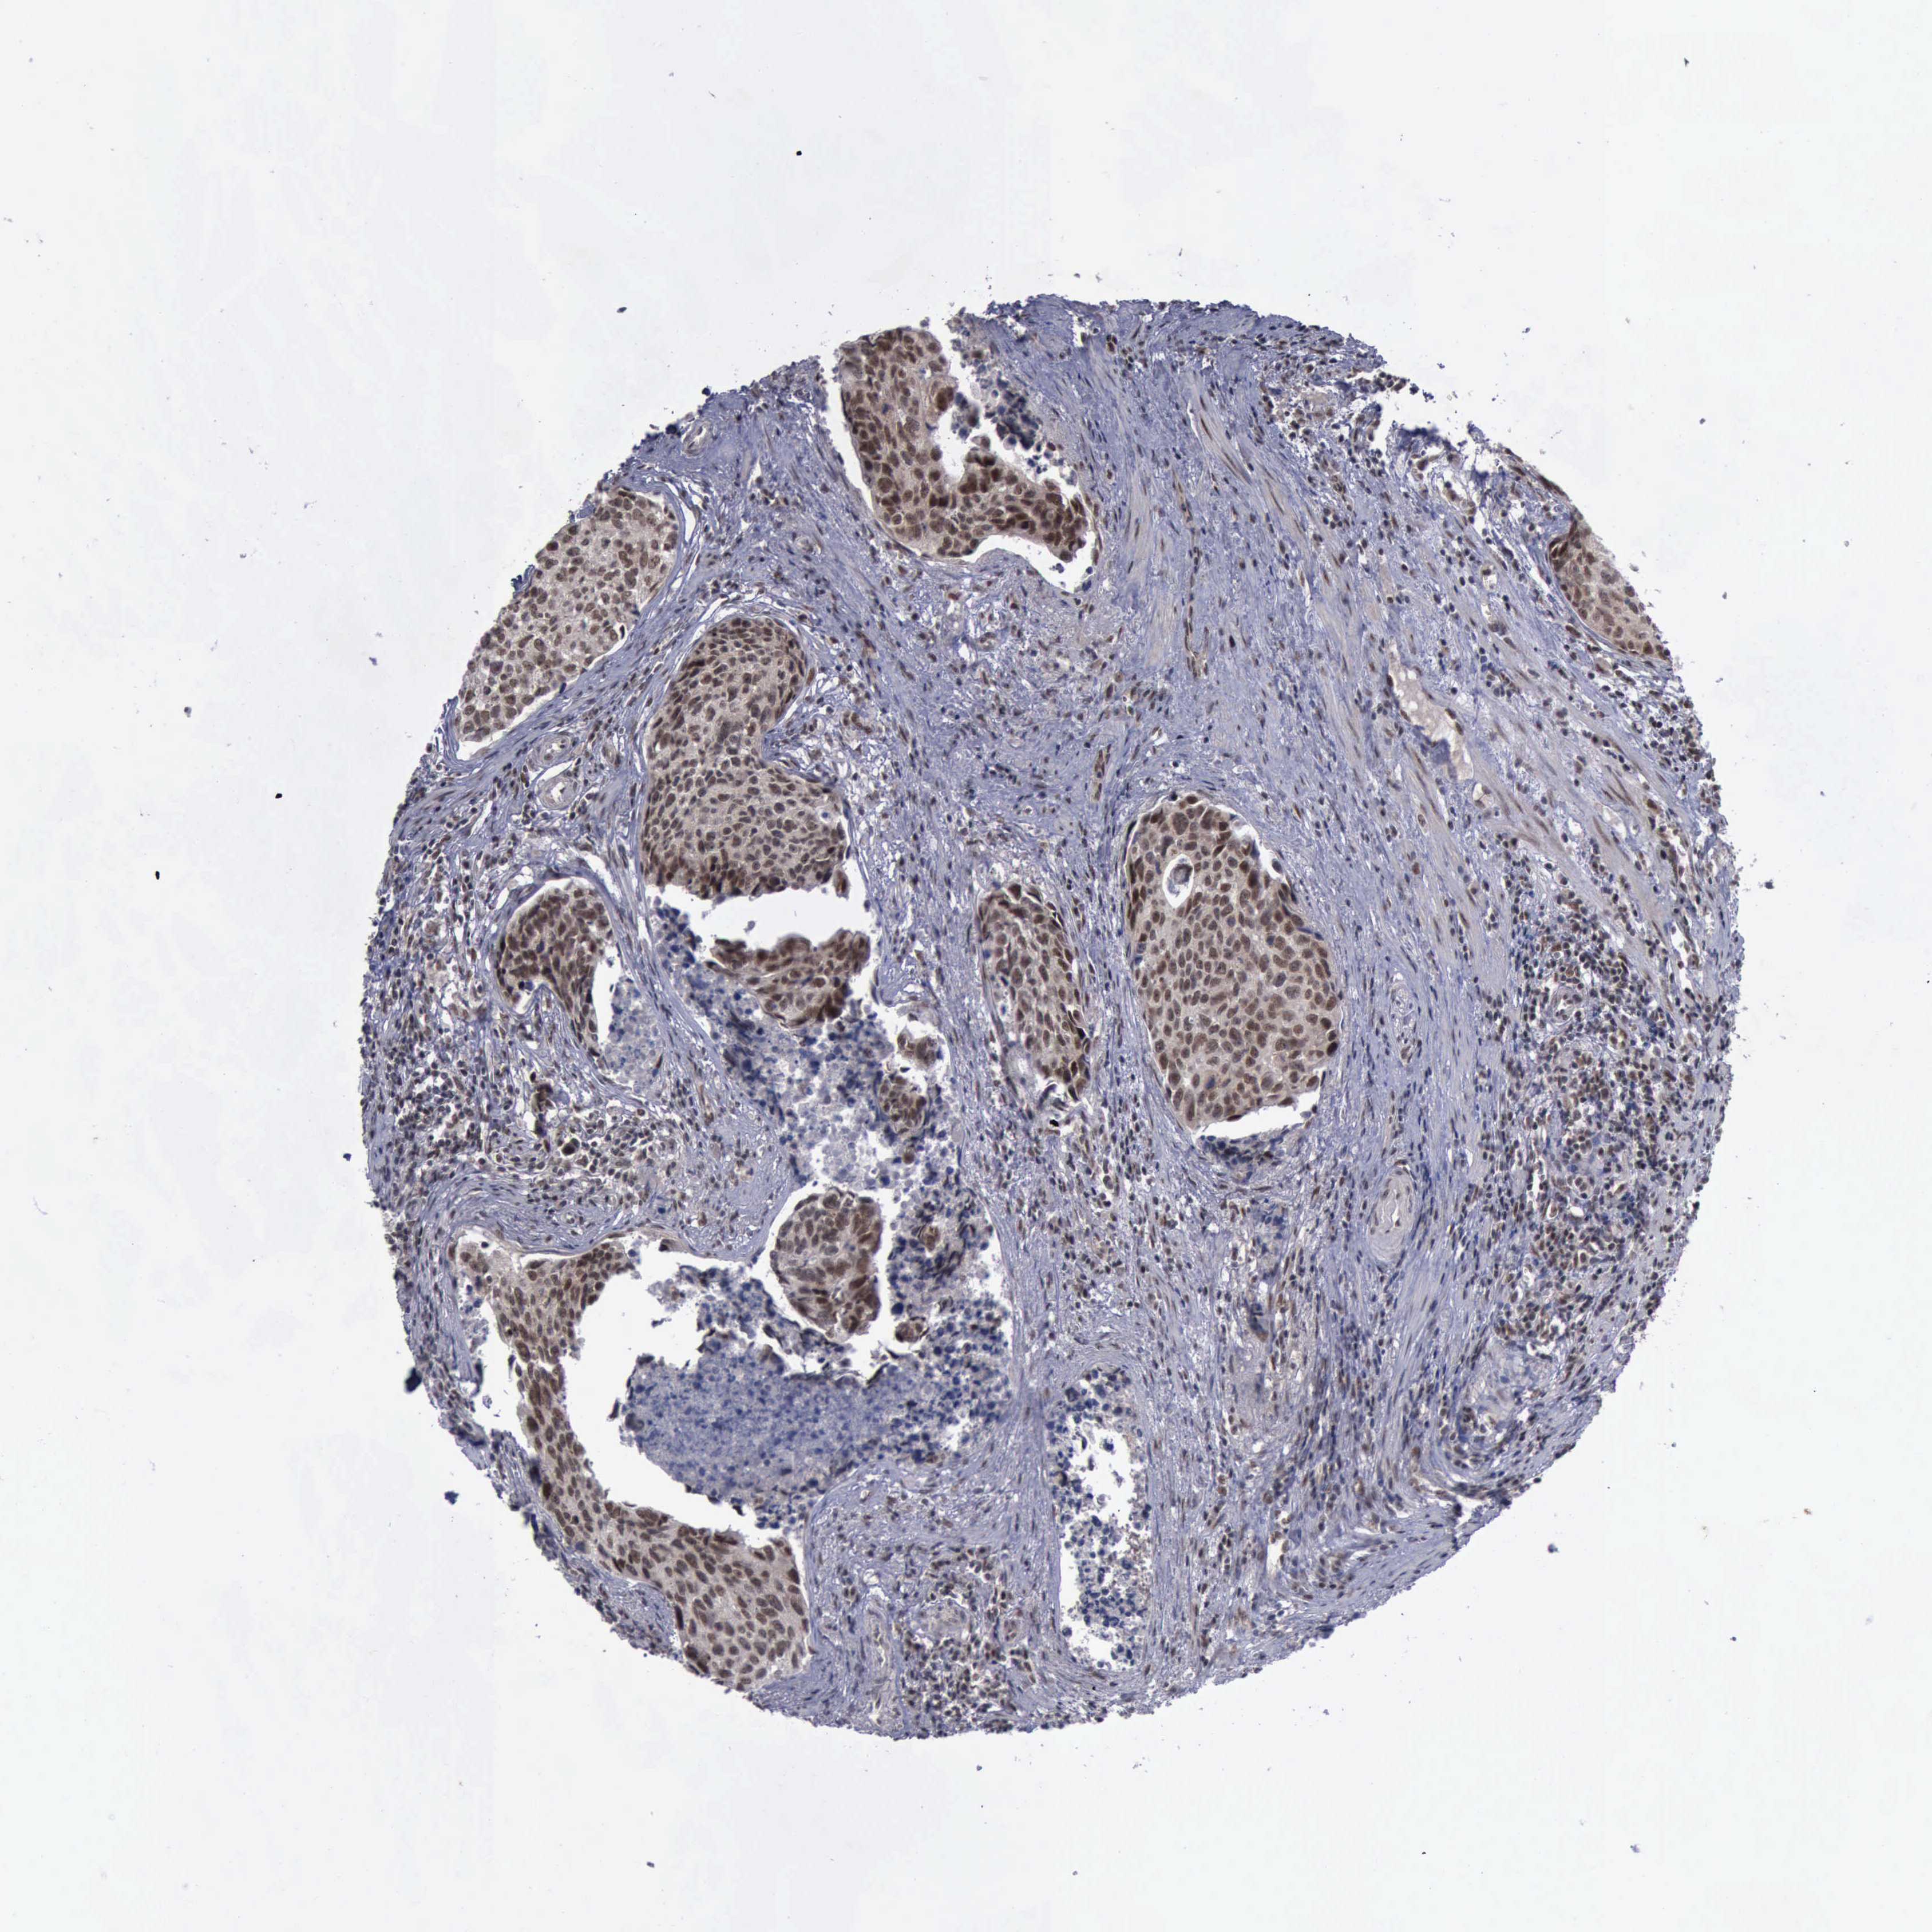

UROTHELIAL CANCER - Protein expressioni

A mouse-over function shows sample information and annotation data. Click on an image to view it in a full screen mode. Samples can be filtered based on level of antibody staining by selecting one or several of the following categories: high, medium, low and not detected. The assay and annotation is described here.

Antibody stainingi

Antibody staining in the annotated cell types in the current human tissue is reported as not detected, low, medium, or high, based on conventional immunohistochemistry profiling in selected tissues. This score is based on the combination of the staining intensity and fraction of stained cells.

Each image is clickable and will lead to virtual microscopy that enables deeper exploration of all samples and also displays staining intensity scores, fraction scores and subcellular localization as well as patient and tissue information for each sample.

Antibody CAB000102

Antibody CAB080442

Urothelial carcinoma, High grade

Urothelial carcinoma, Low grade

Adenocarcinoma, NOS